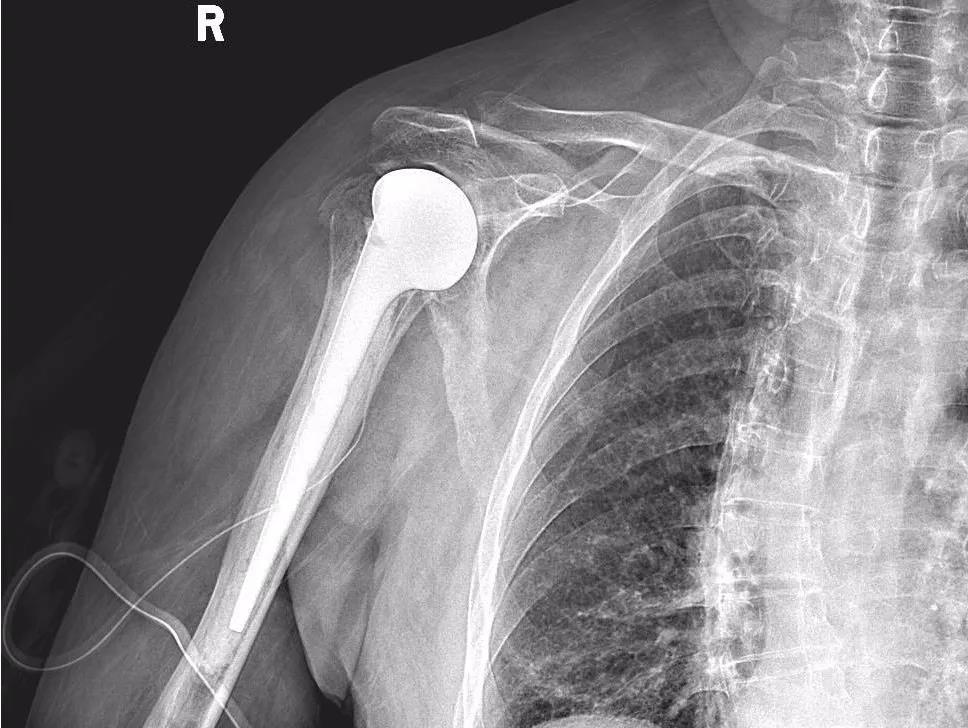

近日,北京大学第三医院延安分院(延安市中医医院)运动医学科团队在庞军主任带领下,成功完成了医院首例人工肱骨头置换术,标志着我院在关节置换领域再上一个新台阶。

“患者右侧肱骨解剖颈骨折合并肩关节脱位,Neer4型,肱骨头缺血坏死风险极大,要想恢复功能,最佳治疗方案需行人工肱骨头置换术。”庞军主任为郝爷爷详细查体,并结合检查结果向家属详细交代患者病情和下一步治疗方案。

1月26日,由运动医学科主任庞军主刀,为郝爷爷顺利实施了医院首例人工肱骨头置换术,目前郝爷爷恢复良好,过年前已顺利出院,安安心心过新年。

运动医学科主任庞军介绍说,人工肱骨头置换术适应症为大于60岁,肱骨大小结节无法重建或肱骨头坏死、难治性肩袖损伤及严重骨关节炎。人工肱骨头置换术,是较为先进的手术操作,对手术操作的准确性和熟练度有严格要求,目前在地市级医院开展较少,总体适应症较窄且患者相对其他关节置换较少。